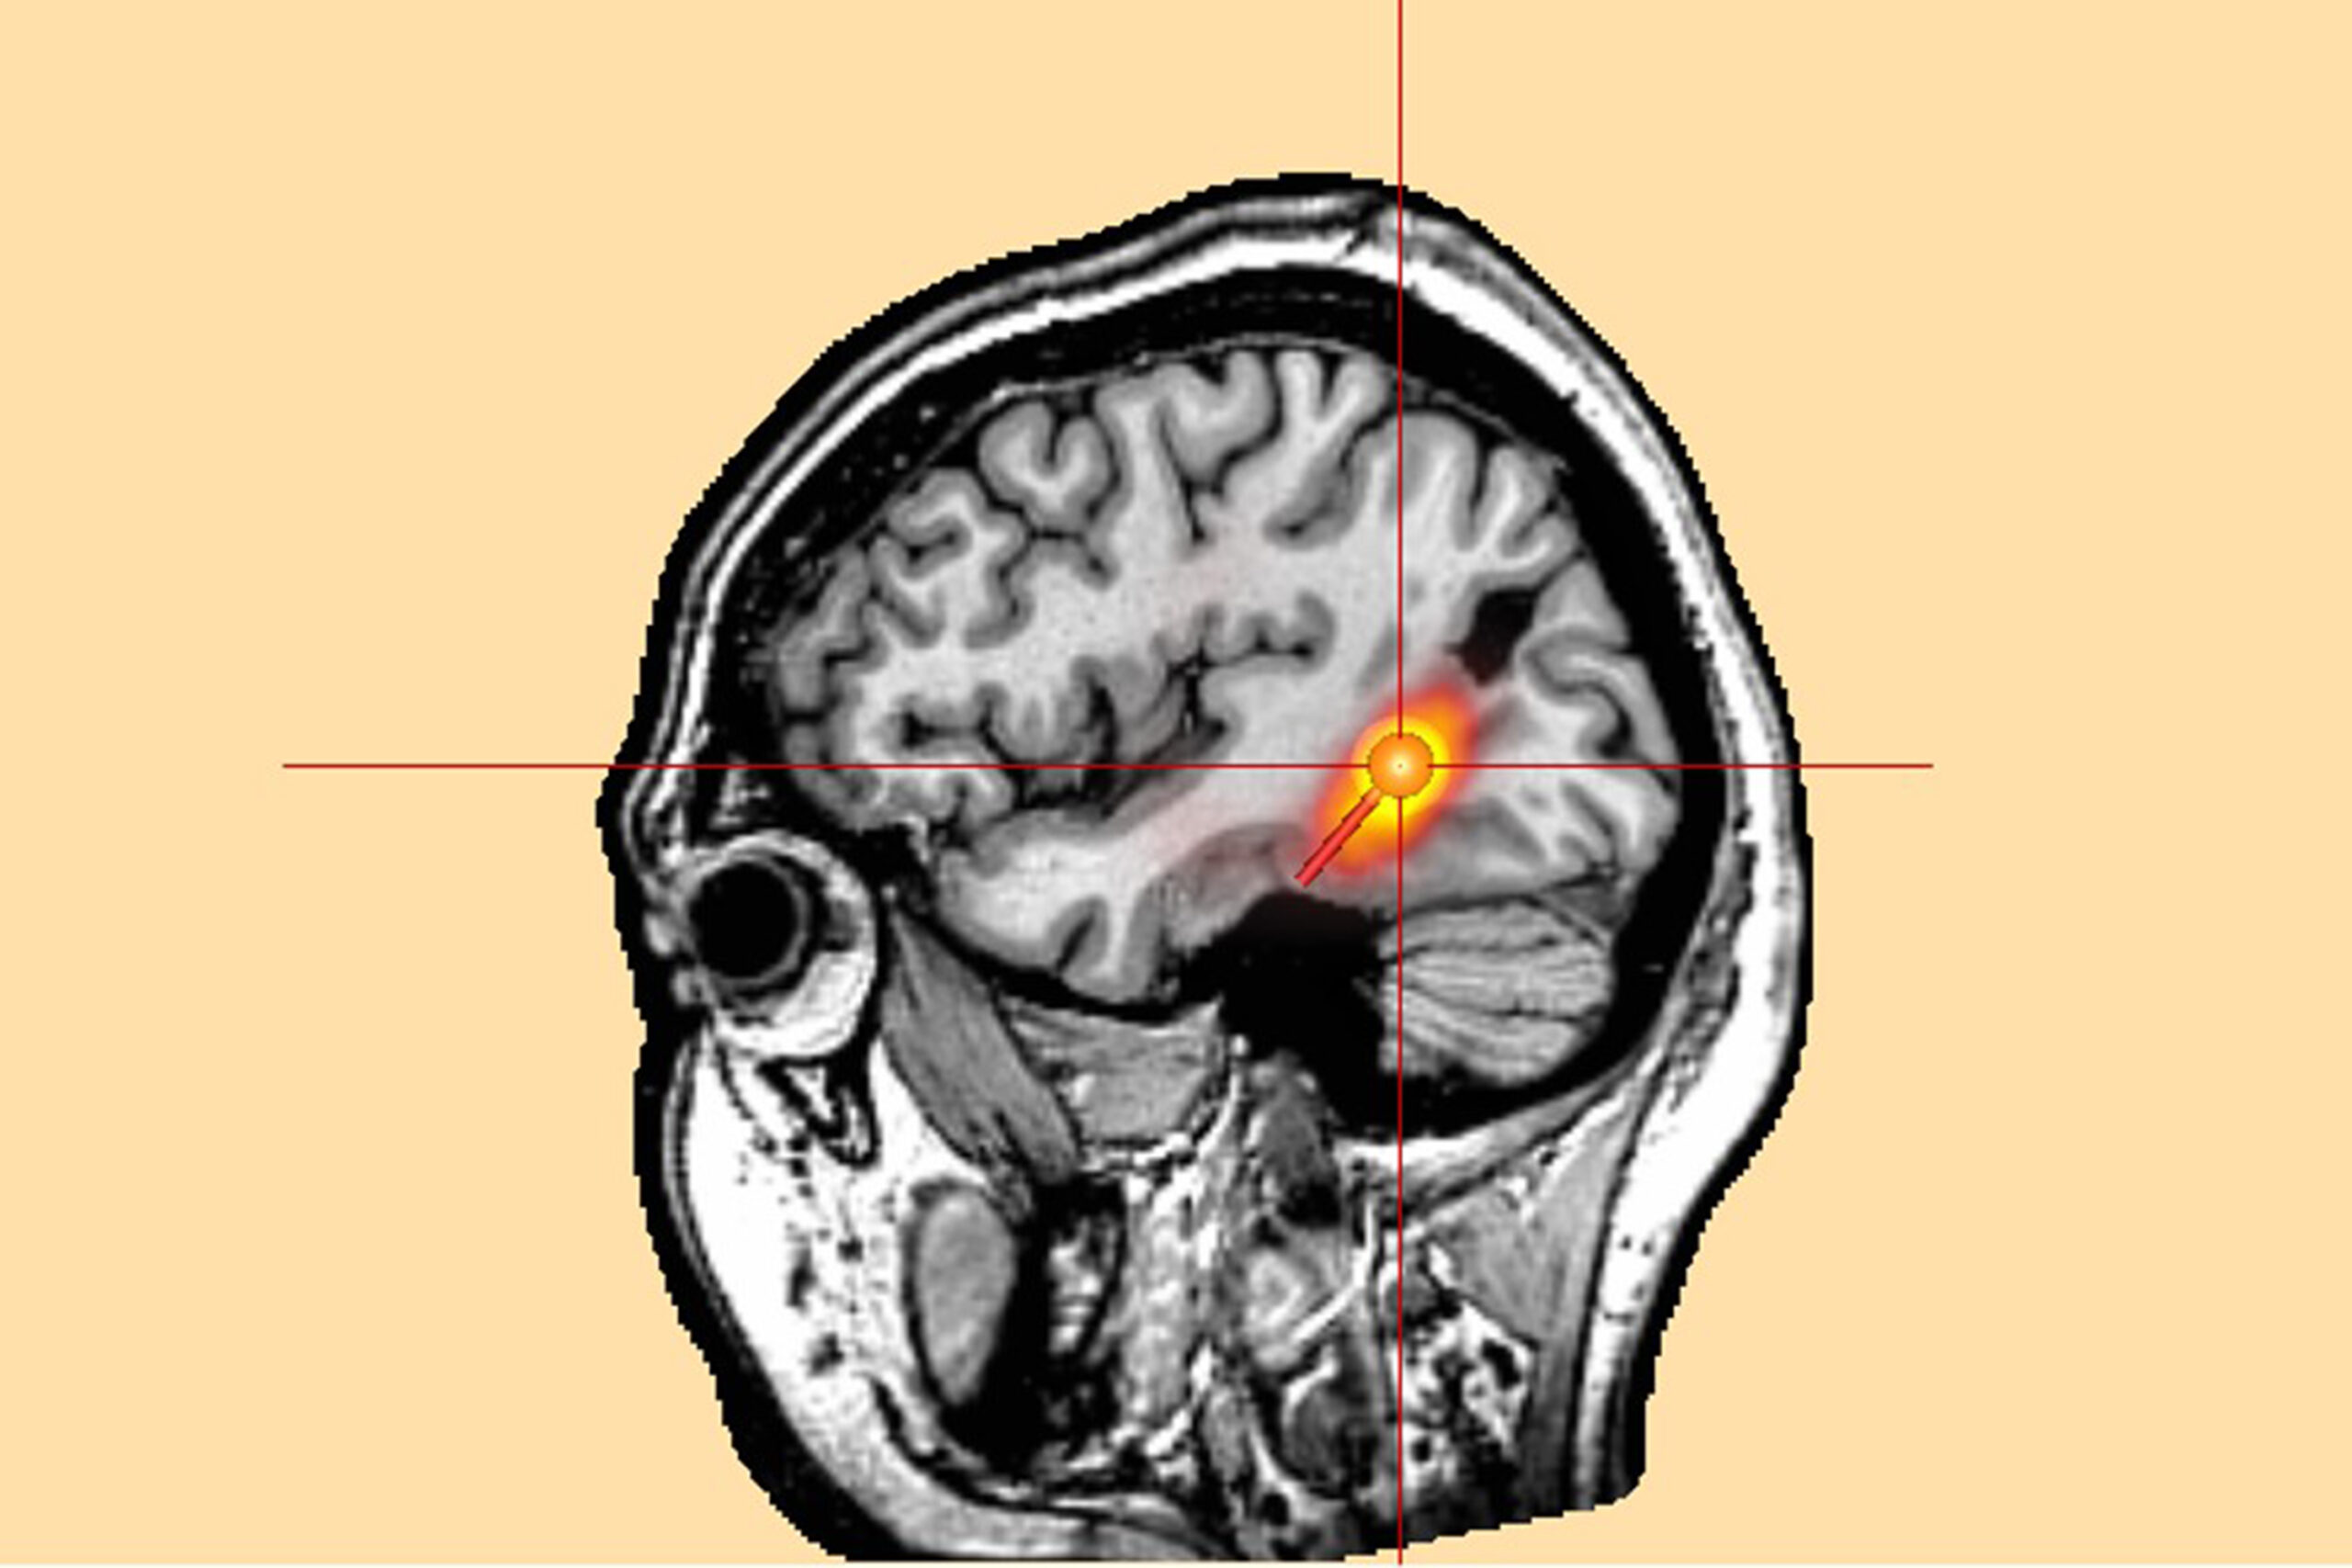

Um das gefundene Epilepsieareal in einem 3-D-Bild des Gehirns zu verorten, kombinieren die Ärztinnen und Ärzte des Erlanger Epilepsiezentrums die MEG mit den Schichtbildern der Magnetresonanztomografie (MRT). So erhalten sie eine dreidimensionale „Landkarte“ des Gehirns mit genau markierter Epilepsieregion.